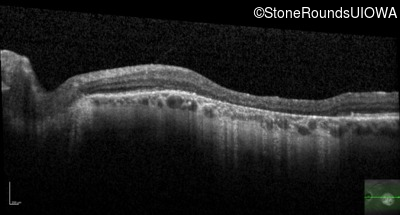

Optical Coherence Tomography - Right - 20/50 -1

Exemplar / OCT Stack

OCT Stack